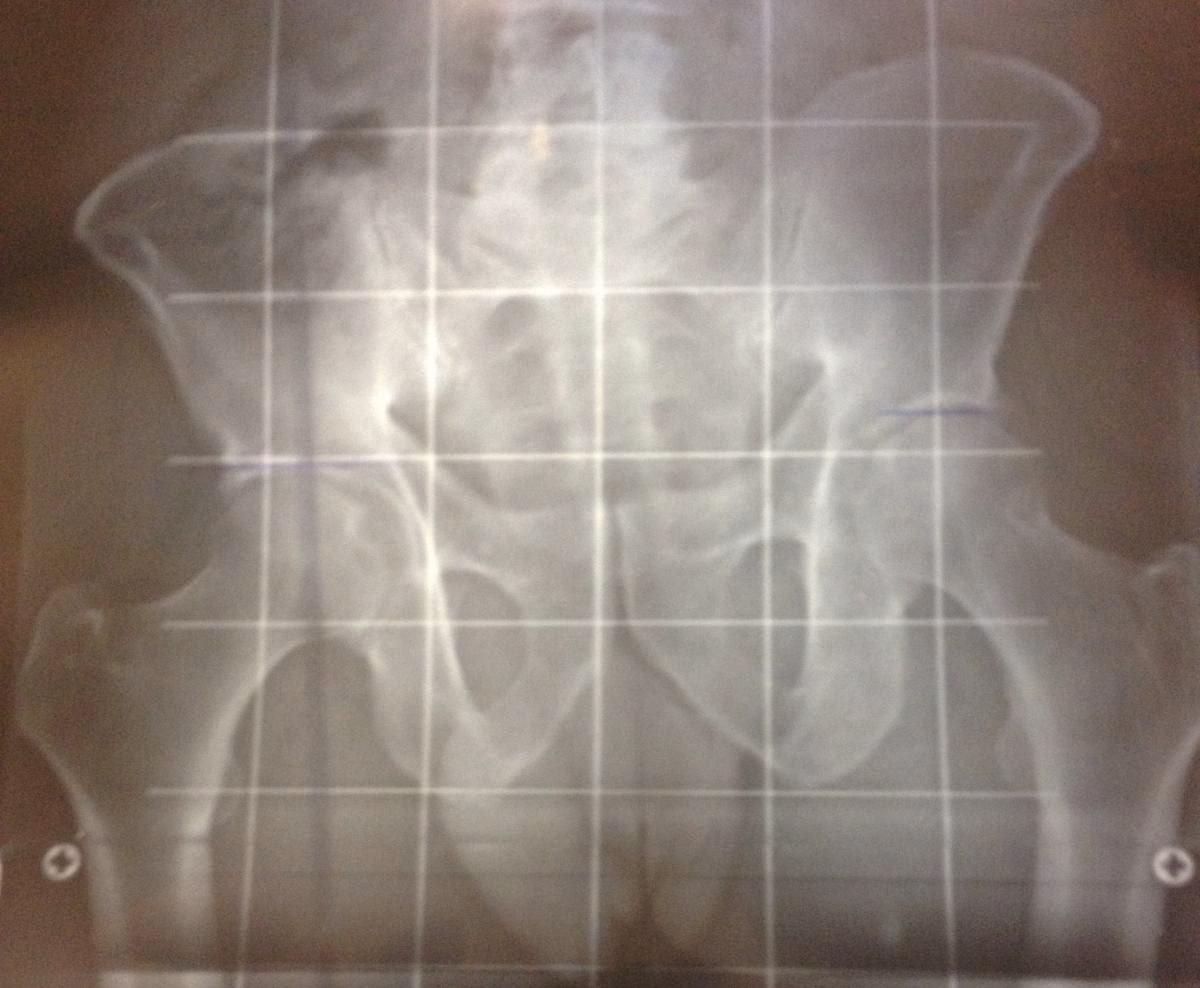

Pruebas Diagnósticas por Imagen: La Telemetría

Cuando se sospecha una dismetría real significativa (generalmente superior a 0.5 cm) o cuando la evaluación clínica no es concluyente, se recurre a pruebas diagnósticas por imagen para obtener una medición precisa de la longitud ósea.

La Telemetría es la prueba de referencia para medir la dismetría ósea. Consiste en una radiografía de cuerpo entero o de las extremidades inferiores que abarca desde la pelvis hasta los tobillos. Se toman medidas precisas de la longitud de los huesos (fémur y tibia) en cada pierna, permitiendo calcular con exactitud la diferencia de longitud real entre ellas. Esta prueba es objetiva y proporciona datos milimétricos, eliminando la variabilidad de las mediciones clínicas.

Otras pruebas de imagen como la tomografía computarizada (TC) también pueden utilizarse para mediciones óseas precisas, pero la telemetría es la más comúnmente empleada específicamente para este propósito.